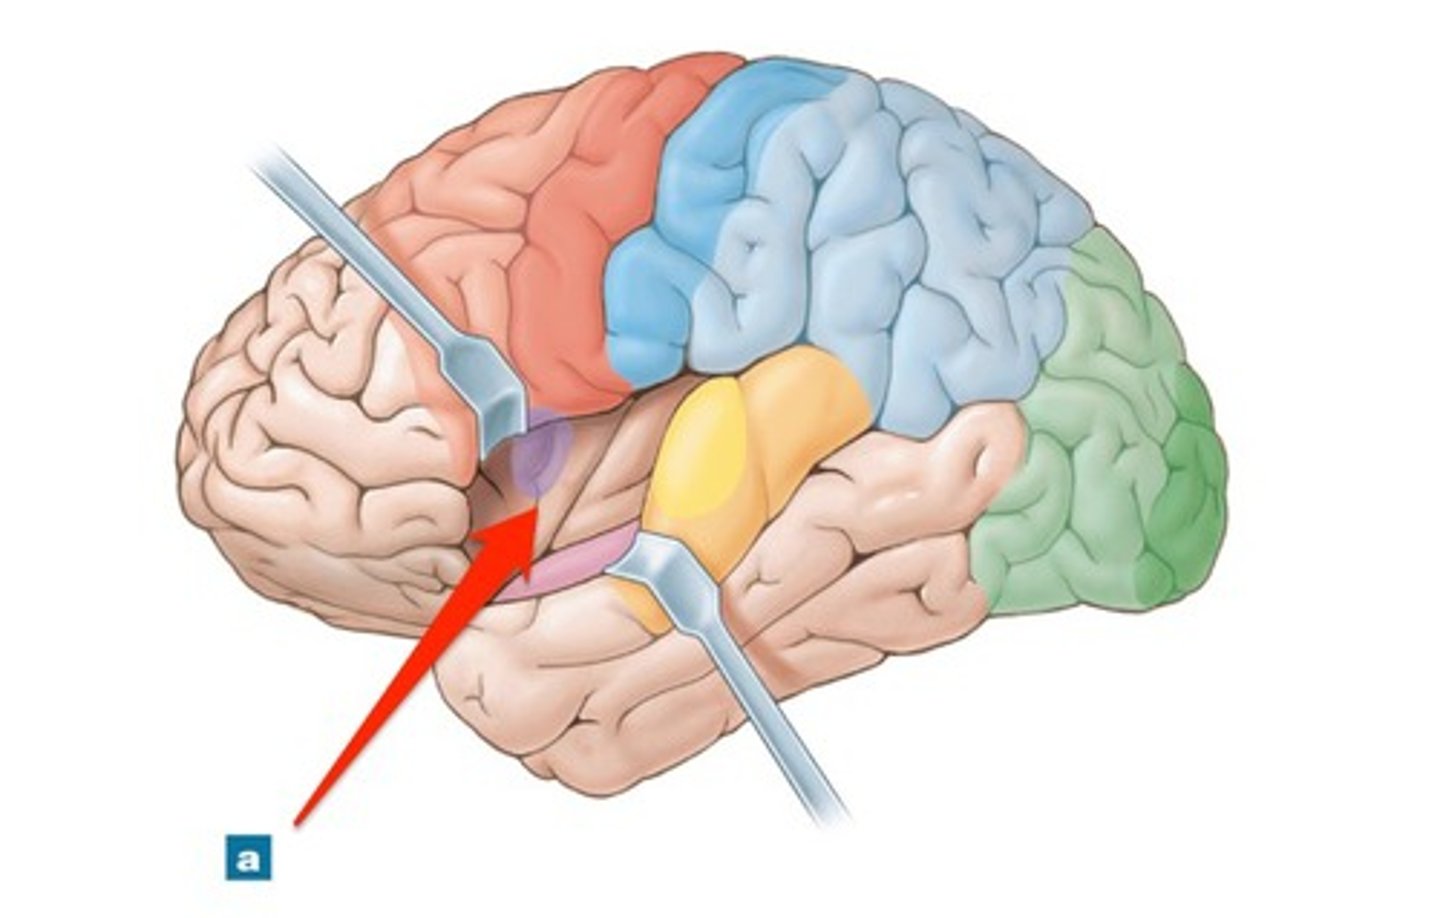

insula

cerebral lobe located deep within lateral sulcus

lateral sulcus

Separates temporal lobe from parietal and frontal lobes

primary gustatory cortex

•Located within insula

•Receives, processes, stores taste information